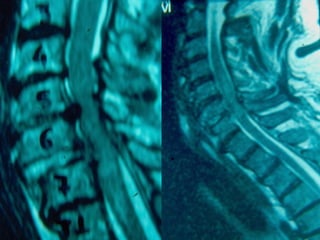

MMRRII

–UUsseeffuull ttoo eevvaalluuaattee

ddiissccrreeppaannccyy

bbeettwweeeenn cclliinniiccaall

eevvaalluuaattiioonn aanndd xx--

rraayy // CCTT ffiinnddiinnggss

–DDiisscc hheerrnniiaattiioonn

–LLiiggaammeennttoouuss

iinnjjuurryy